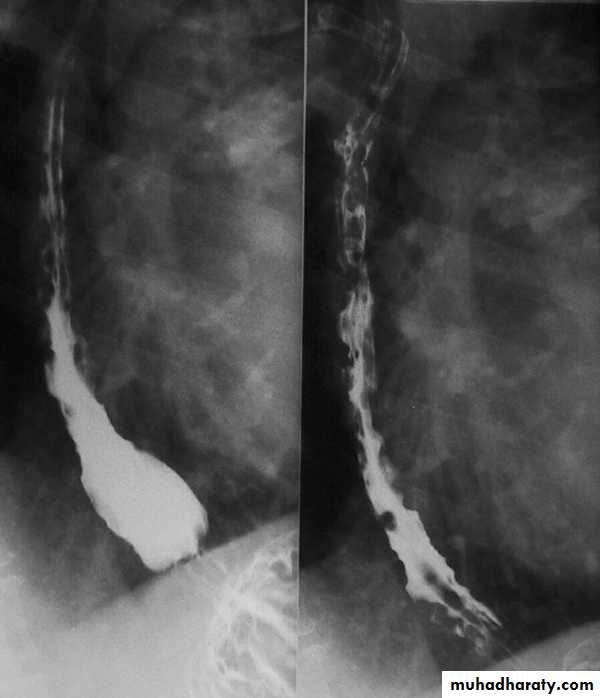

Esophageal Varieces

Dilatation of venous plexus in the wall of the esophagus due to increased pressure ( portal H.T.).

Important cause of Hematemesis .

Early changes seen in the mucosa (D.C.) loss of parallelism with thick and tortuous folds.

Later multiple small filling defects (fine cobble stone).

In advanced stage large filling defects ( coarse cobble stone ) .

7More advanced stage elongated and worm like filling defect .

The changes are seen at lower third and gastric fundus.